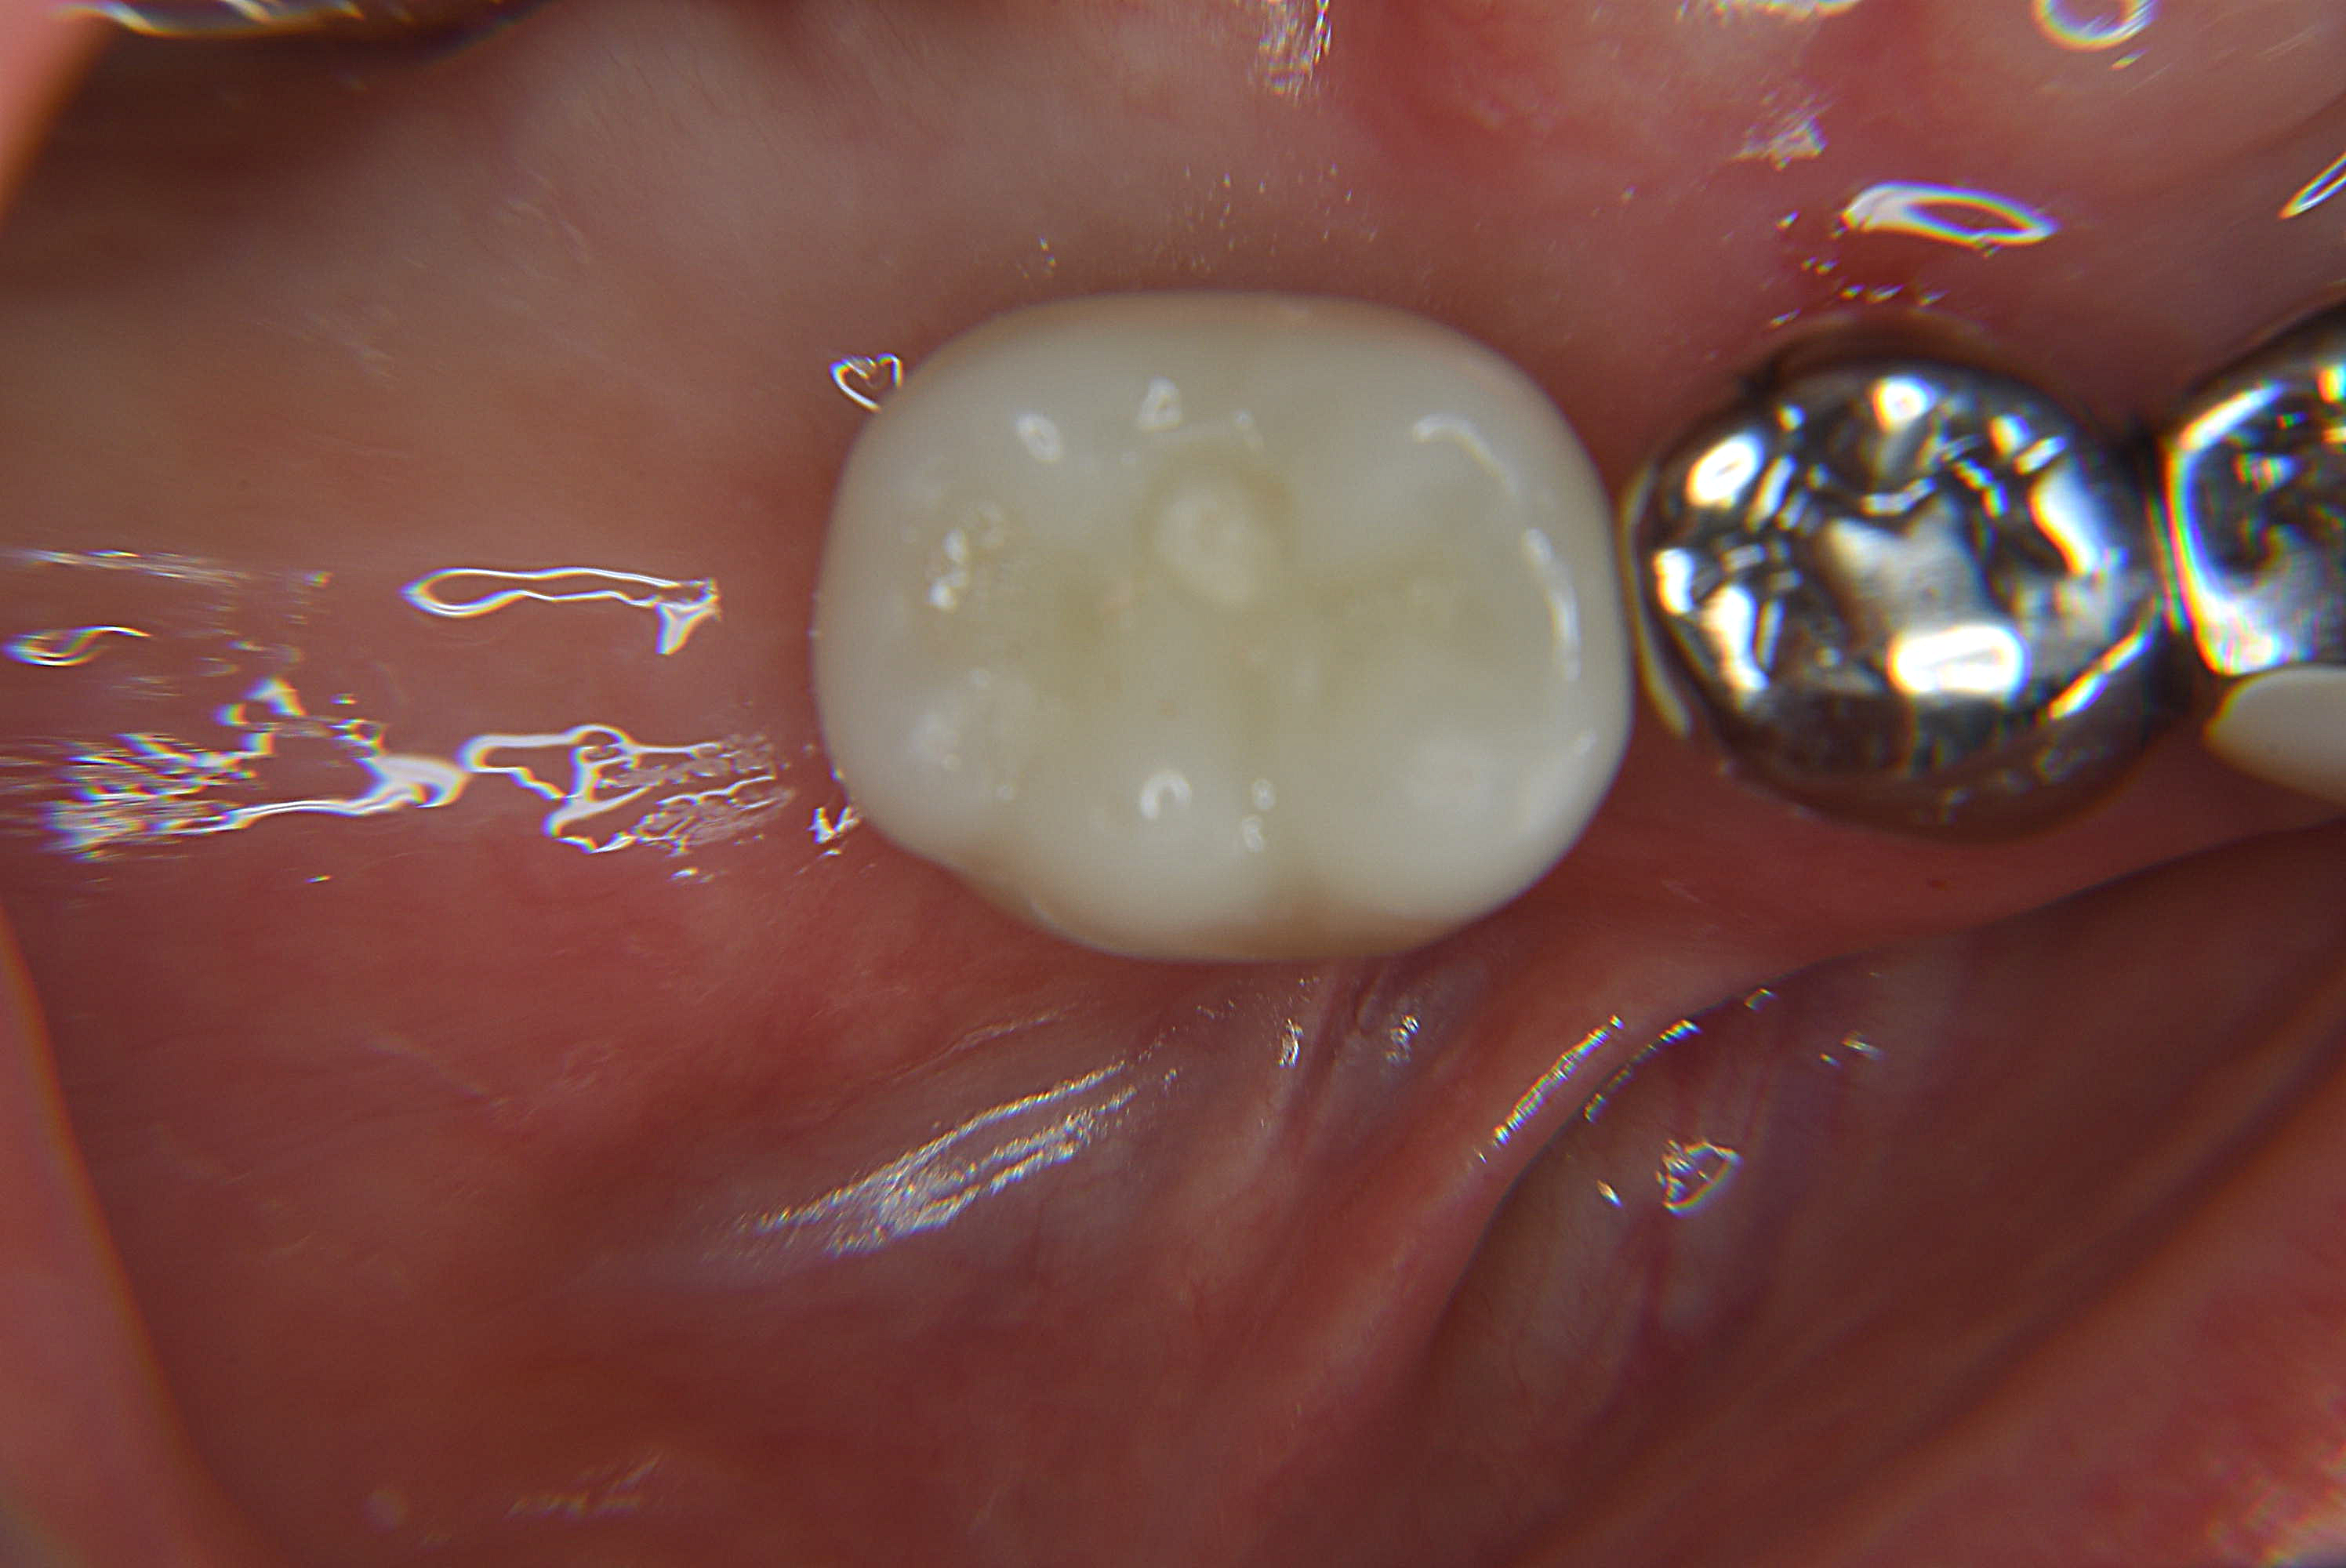

装着後

| 装置名 | インプラント+ジルコニアCr(エコノミー) |

| リスク | 外科手術が必要になるので、腫れや痛み等のリスクについてしっかりと説明を行いました。 歯肉の状態も良かったので、フラップレス(歯茎を切ってめくらず)手術を選択し、手術後の経過観察では痛みが最小限で腫れも少なく安堵されていました。 最終の被せ物装着前の歯茎の治り方とそれに調和したオーダーメイドの被せ物を作成し、装着した日は自然な見た目と入れ歯ではなかった噛みやすさに大変喜ばれていました。 |